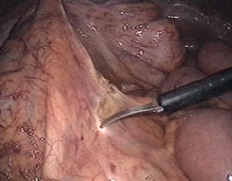

大腸についている血管の入った膜(腸間膜といいます)を切り開き、腸に行く血管を処理する(切り離す)準備をします。

もともととても粗くくっついている膜なので、ほとんど血が出ることなく、この膜をはがすことができます。

肛門側の大腸をはがし、切り離しをスムーズにするために切り離し予定部分の腸を充分露出しておきます。